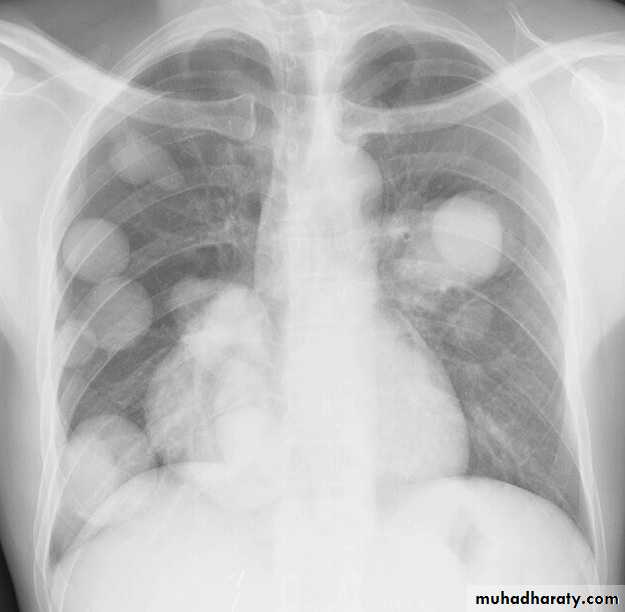

Cannon ball secondaries